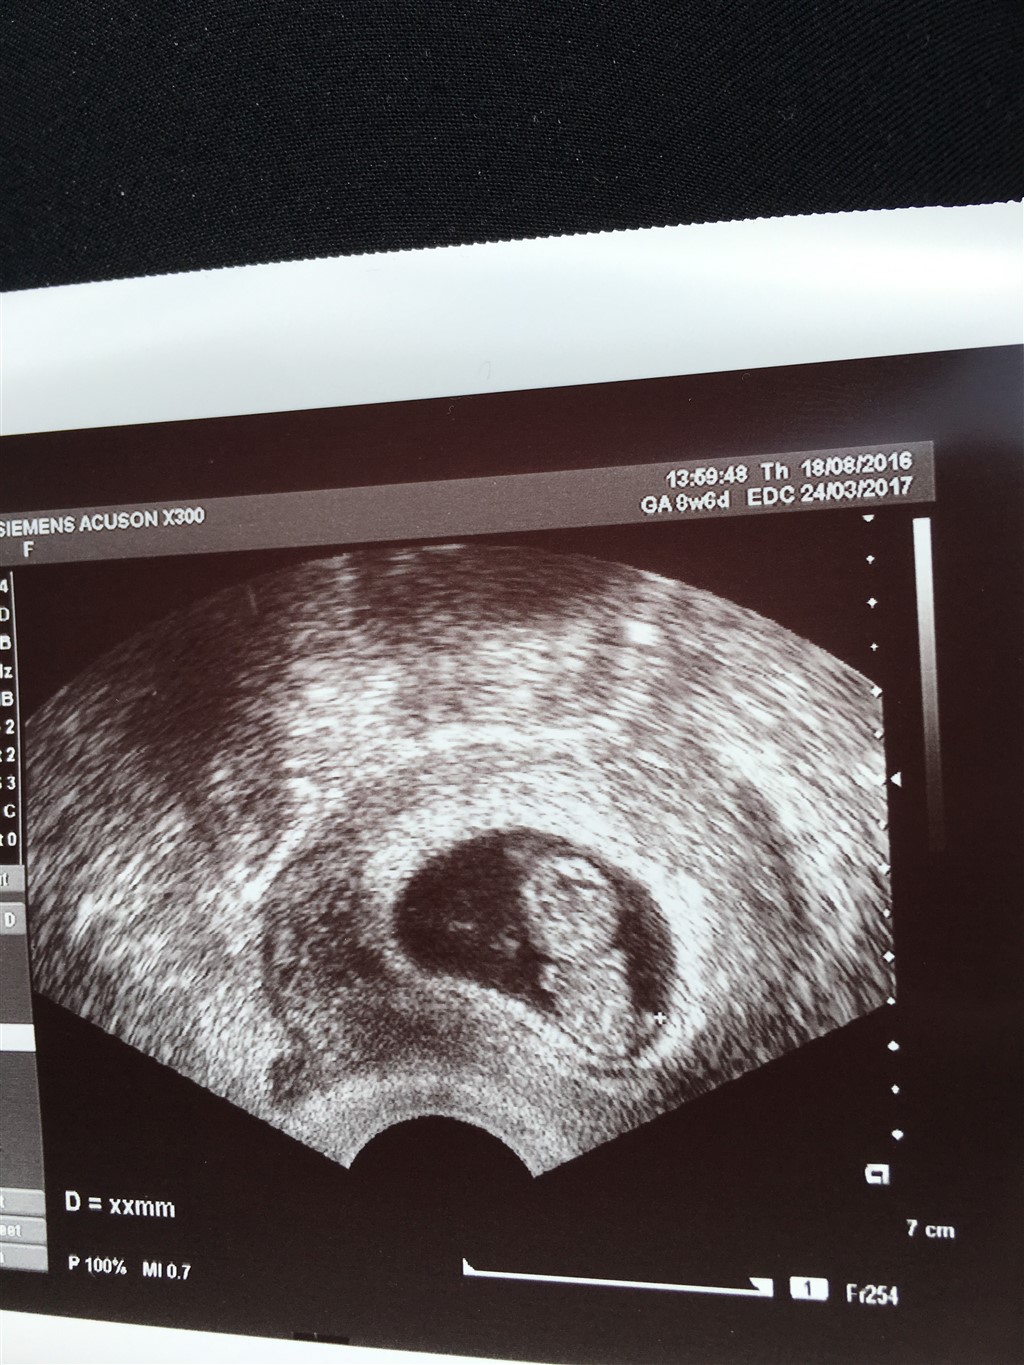

ja var til en scanning da jeg var 7 uger på klinikken da jeg havde blødt lidt i uge 5 men alt så fint ud og kom så til en ekstra scanning i uge 9 hvor vi kunne se bebs bevæge sig så bliver man bare solgt

Mille:) skriver: Hvor dejligt de gør det mandag istedet ja var til en scanning da jeg var 7 uger på klinikken da jeg havde blødt lidt i uge 5 men alt så fint ud og kom så til en ekstra scanning i uge 9 hvor vi kunne se bebs bevæge sig så bliver man bare solgt